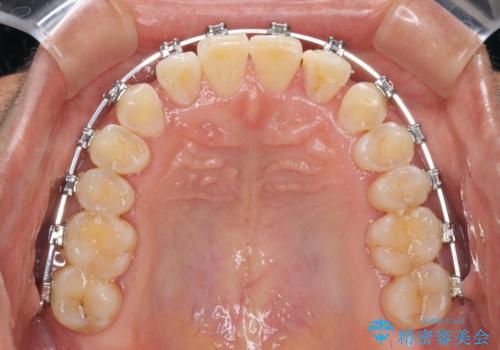

反対咬合の改善 途中で出産をしながらワイヤー矯正

- 矯正装置

- メタルブラケット

マウスピース矯正も提案しましたが、しっかりと使用する自信がないとのことで、ワイヤー装置により矯正治療を行うこととしました。

咬合力が強く、反対咬合の改善に時間がかかりましたが、その後はスムーズに進めることができました。

途中、妊娠と出産があり、治療が中断したため、治療期間は延びましたが、出産も矯正治療も無事に終えることができました。